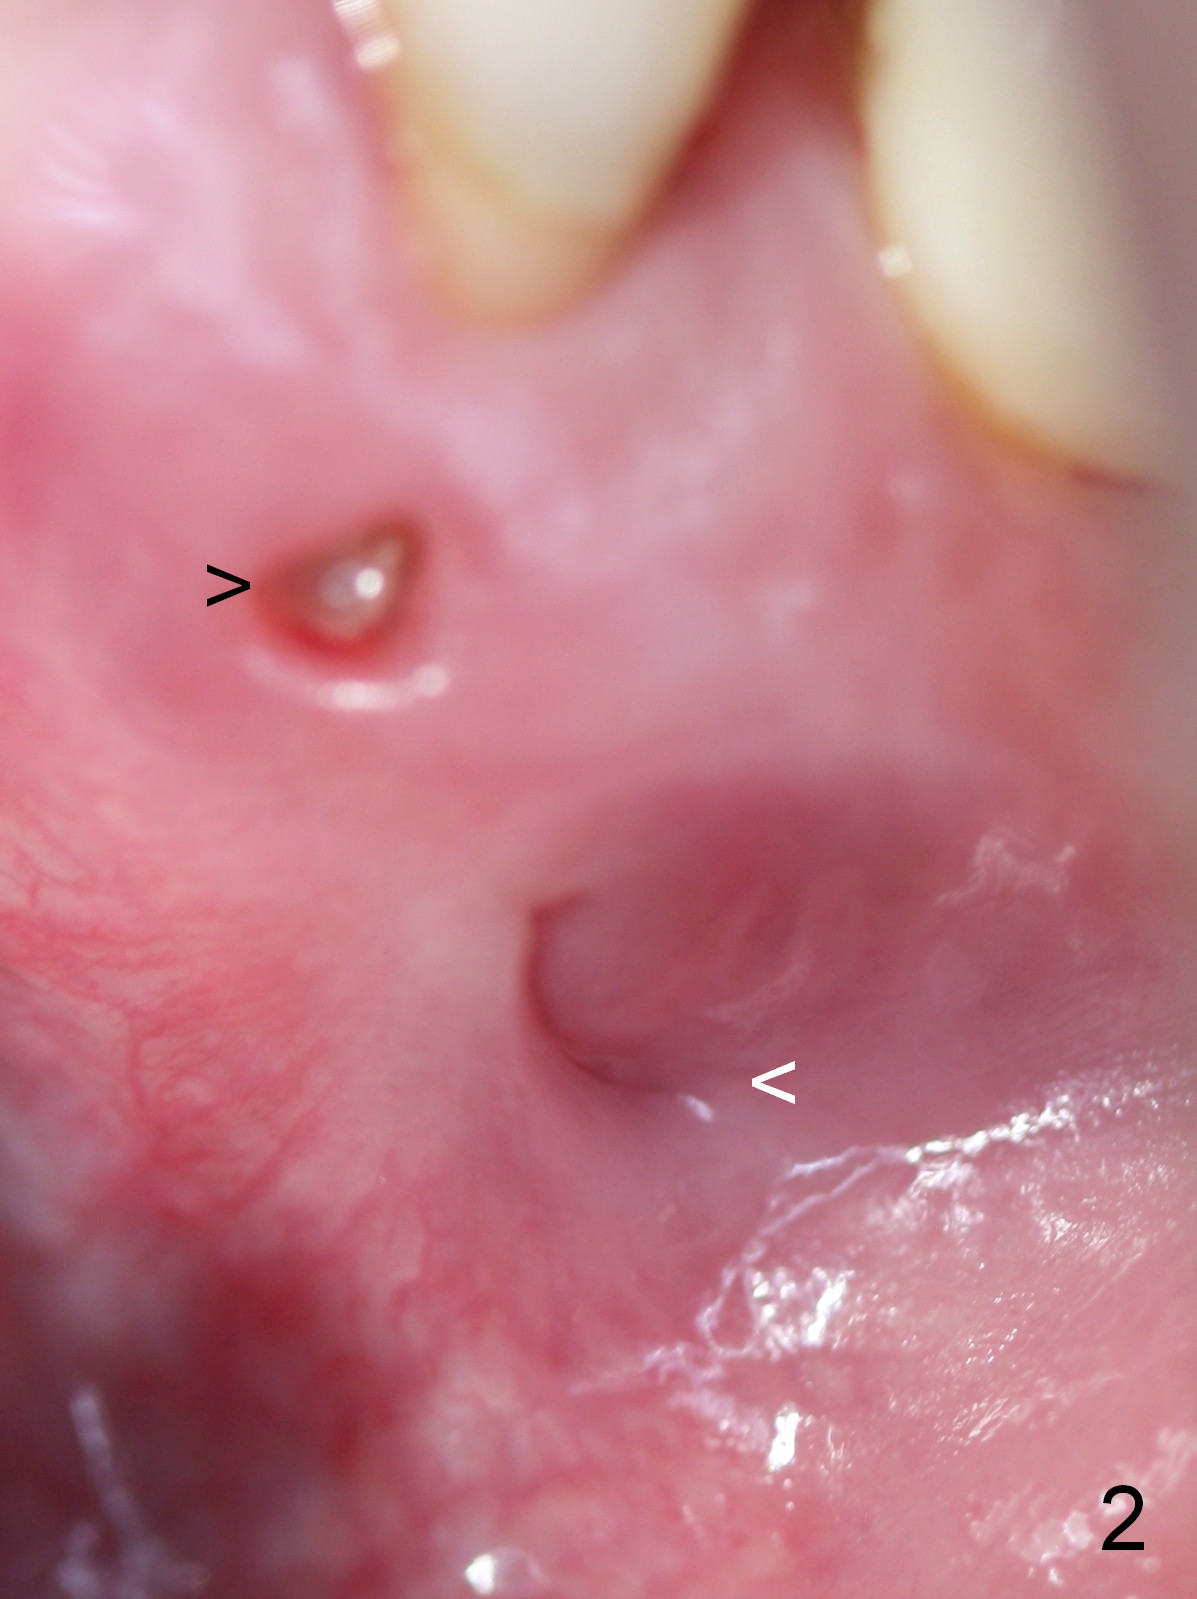

A 45-year-old man (JT) has endo failure at #20 with fenestration (Fig.1,2 black >) and fistula (white <). Insertion of a Gutta Percha at the fistula (Fig. 3 <; PA taken 2 years ago) indicates that the infection is dervied from the apex of the tooth #20. The socket will be soaked with 2% Xylo, 1:50,000 Epinephrine gauze. A 4.5x17 mm tissue-level (Fig.4) or 14 mm bone-level implant is placed as lingual as possible (Fig.5 green). If primary stability is achieved, an abutment is placed (pink). A large piece of resorbable membrane is used to cover the buccal defect (including buccal recession, fenestration and fistula (Fig.6 yellow dashed line). Two small pieces of non-resorbable membrane are placed to cover the gingival recession and the fenestration (Fig.7 white dashed line, buried underneath the edge of the gigniva). Then place bone graft buccally. Place a small piece of gauze (one layer) or plastic (from Tatum implant bag) over the 2nd membrane over the gingival recession and fabricate an immediate provisional. When the acrylic is partially set, remove the gauze or plastic from the provisional. After trimming and polishing, the provisional is cemented to securely keep the 2nd membrane in place. When the wound is healing and the 2nd membrane is stable, trim the buccal extension of the provisional. It is expected that the buccal hard and soft tissue will regenerate over the implant.